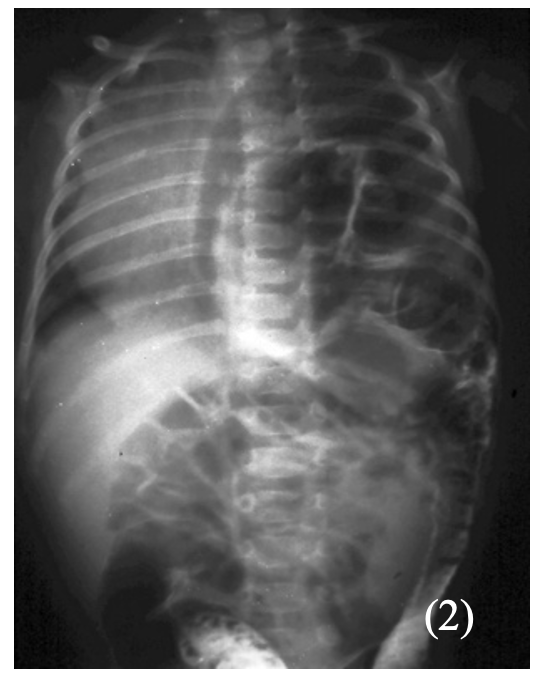

Congenital Diaphragmatic Hernia

This is a condition where the abdominal organs herniate a foramen in the diaphragm

– Most cases occur on the left-side and lead to compression of the lungs

– It occurs due to a failure of the pleuroperitoneal folds which form the diaphragm to seal, which leaves an opening through which the organs can pass through

– This allows the abdominal organs such as the bowel to pass through into the thorax

Symptoms:

– Pulmonary hypoplasia –> causes respiratory distress (SOB, cyanosis)

– Poor air entry into the left chest

– Raised blood pressure

– Apex beat and heart sounds displaced to right

Diagnosis:

– X-ray chest and abdomen shows loops of bowel in the chest:

Management:

Image 2: © Nevit Dilmen, CC BY-SA 3.0 <https://creativecommons.org/licenses/by-sa/3.0>, via Wikimedia Commons